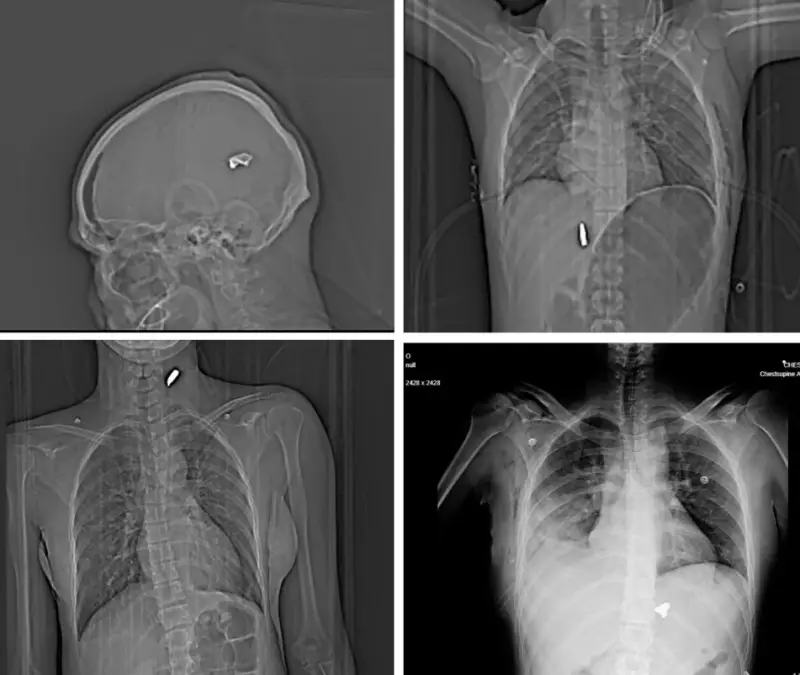

وأظهرت هذه الصور التي تجاوز عددها 75 فحصا بالأشعة السينية والتصوير المقطعي، أنماطا مروعة من الإصابات الناجمة عن استخدام بنادق هجومية وطلقات صيد معدنية ضد المحتجين.

وأظهرت الفحوصات إصابات قاتلة أخرى بينها رصاصة كبيرة العيار استقرت في دماغ رجل منتصف العمر، وأخرى مزقت القصبة الهوائية لشاب إضافة إلى إصابات في العمود الفقري والصدر والرئة.

وأكد الخبراء الذين راجعوا هذه الوثائق أن النمط المتكرر للإصابات يشير إلى استهداف مباشر لمناطق حيوية مثل الوجه والصدر والأعضاء التناسلية، وهو ما يعكس نية متعمدة لإحداث إعاقات دائمة.

وأوضحوا أن استخدام "رصاص الطيور" من مسافات قريبة يحول كل طلقة إلى عشرات المقذوفات الصغيرة القادرة على تدمير الأنسجة الرخوة وإحداث نزيف داخلي خطير.